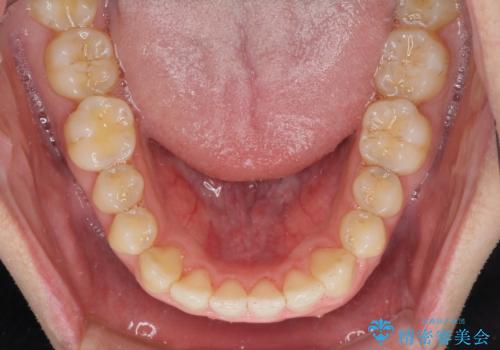

すきっ歯の改善 インビザライン矯正治療

インビザラインにより、上下の歯列を側方に拡大しつつ、前歯の隙間を閉じていくこととしました。

1日22時間の装着時間をしっかりと守ってくださったので、隙間がきれいに閉じ、口元の突出感も改善することができました。